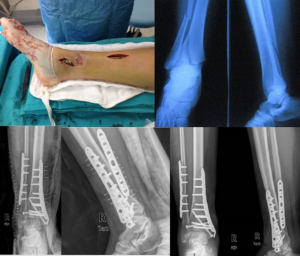

A contemporary method of treating spinal fractures that requires fewer...

Restoring a person's mobility, independence, and general quality of life...